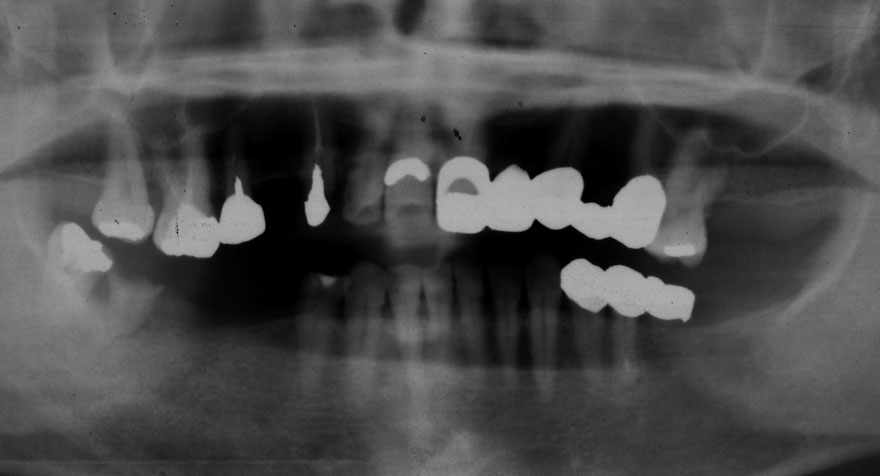

初診時 40歳 女性 平均歯槽骨喪失量:5.24mm

20年後 60歳

平均歯槽骨喪失量:5.79mm

21年間喪失量:-0.55mm

年間喪失速度:-0.027mm

(ケア頻度:1.23ヵ月ごと)